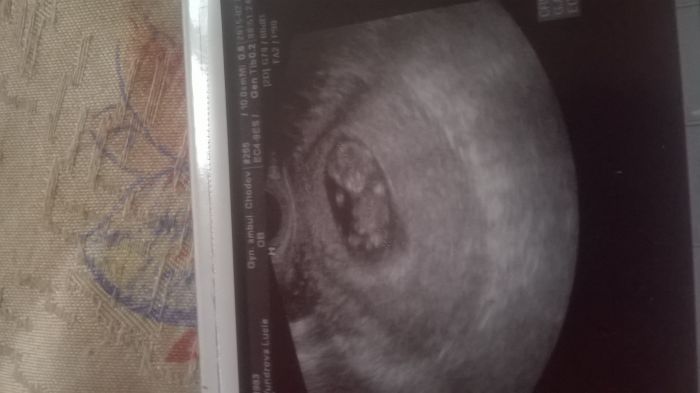

Ahojky děvčátka ;-) tak mam za sebou utz a krev a je vše v pořádku ;-) mimisek je krásnej je velikej 3.83cm a jsem 11+1 termín mam 21.9 ;-) ldyu jsem ho viděla tak mi ukaply slzy stesti..je to krásný pocit..jsem šťastná..i když ten blbecek to posral ale to mi vůbec nevadí ;-) musím se objednat jen na ten screening a na další poradnu je až 1.4 ;-) přikládám foto našeho mimiska ;-)

Hanula,dekuji. ;-) Lucii,to je moc pekna fotecka ;-)

Lucii... super zpravy. Parada. Hezka fotka. Raduj se, preju ti to.